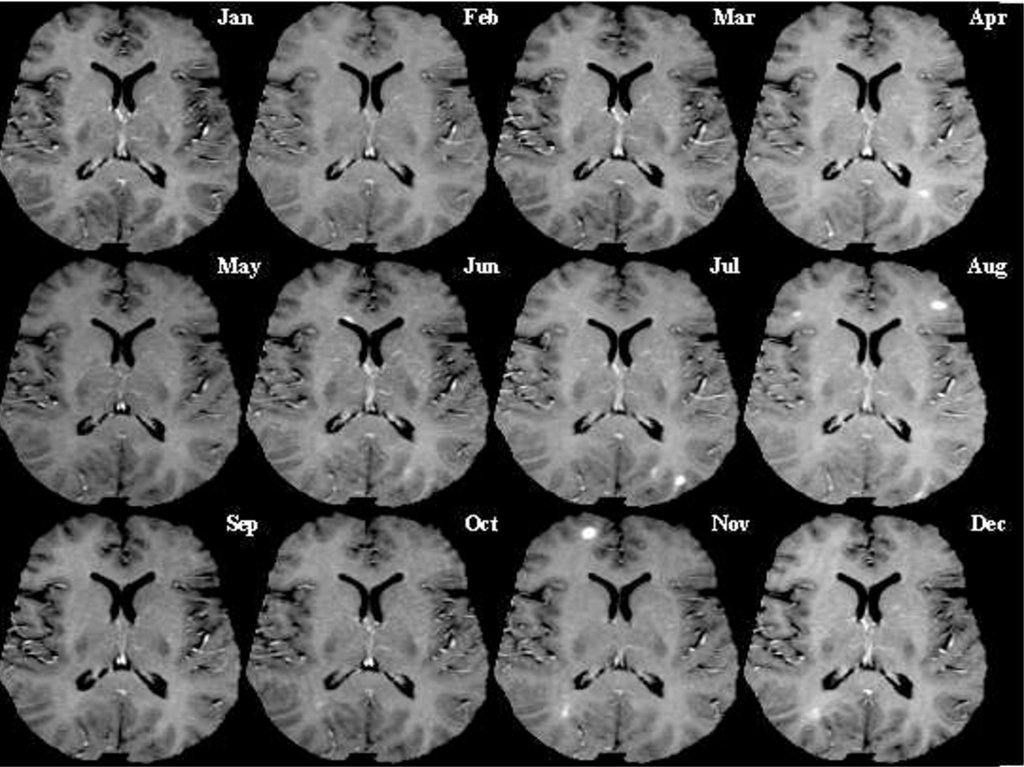

Рассеянный склероз (РС) – хроническое, прогрессирующее

заболевание центральной нервной системы,

патоморфологическую основу которого составляют

процессы демиелинизации нервных проводников

(распад миелиновой оболочки) в головном и спинном

мозге. Клинически РС характеризуется рассеянной

неврологической симптоматикой, слагающейся из

преимущественного поражения оптической,

пирамидной и мозжечковой систем головного и

спинного мозга. В большинстве случаев, особенно на

начальной стадии, течение заболевания

ремиттирующее с последующим переходом в медленнопрогредиентное. Дебютирует РС в молодом возрасте

(20-40 лет), однако не исключается возникновение

заболевания у детей и лиц старше 50 лет.